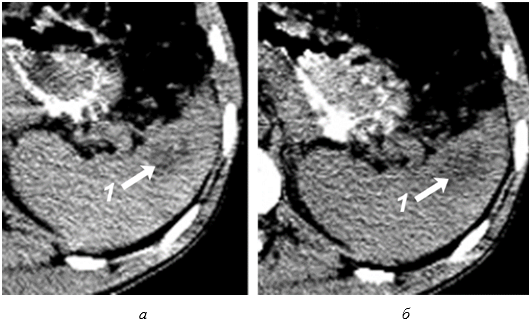

Сканирование селезенки через 8–12 часов после травмы позволяет выявить прогрессирующее неравномерное снижение акустической плотности в зоне интереса (рис. 4, а). Устойчивая визуализация эхонегативной зоны (внутритканевой гематомы) становится возможной по истечении первых суток посттравматического периода (рис. 4, б).

Рис. 4. Эхограмма подкапсульного разрыва селезенки: а – через 8–12 часов после травмы; б – через 1 сутки после травмы.